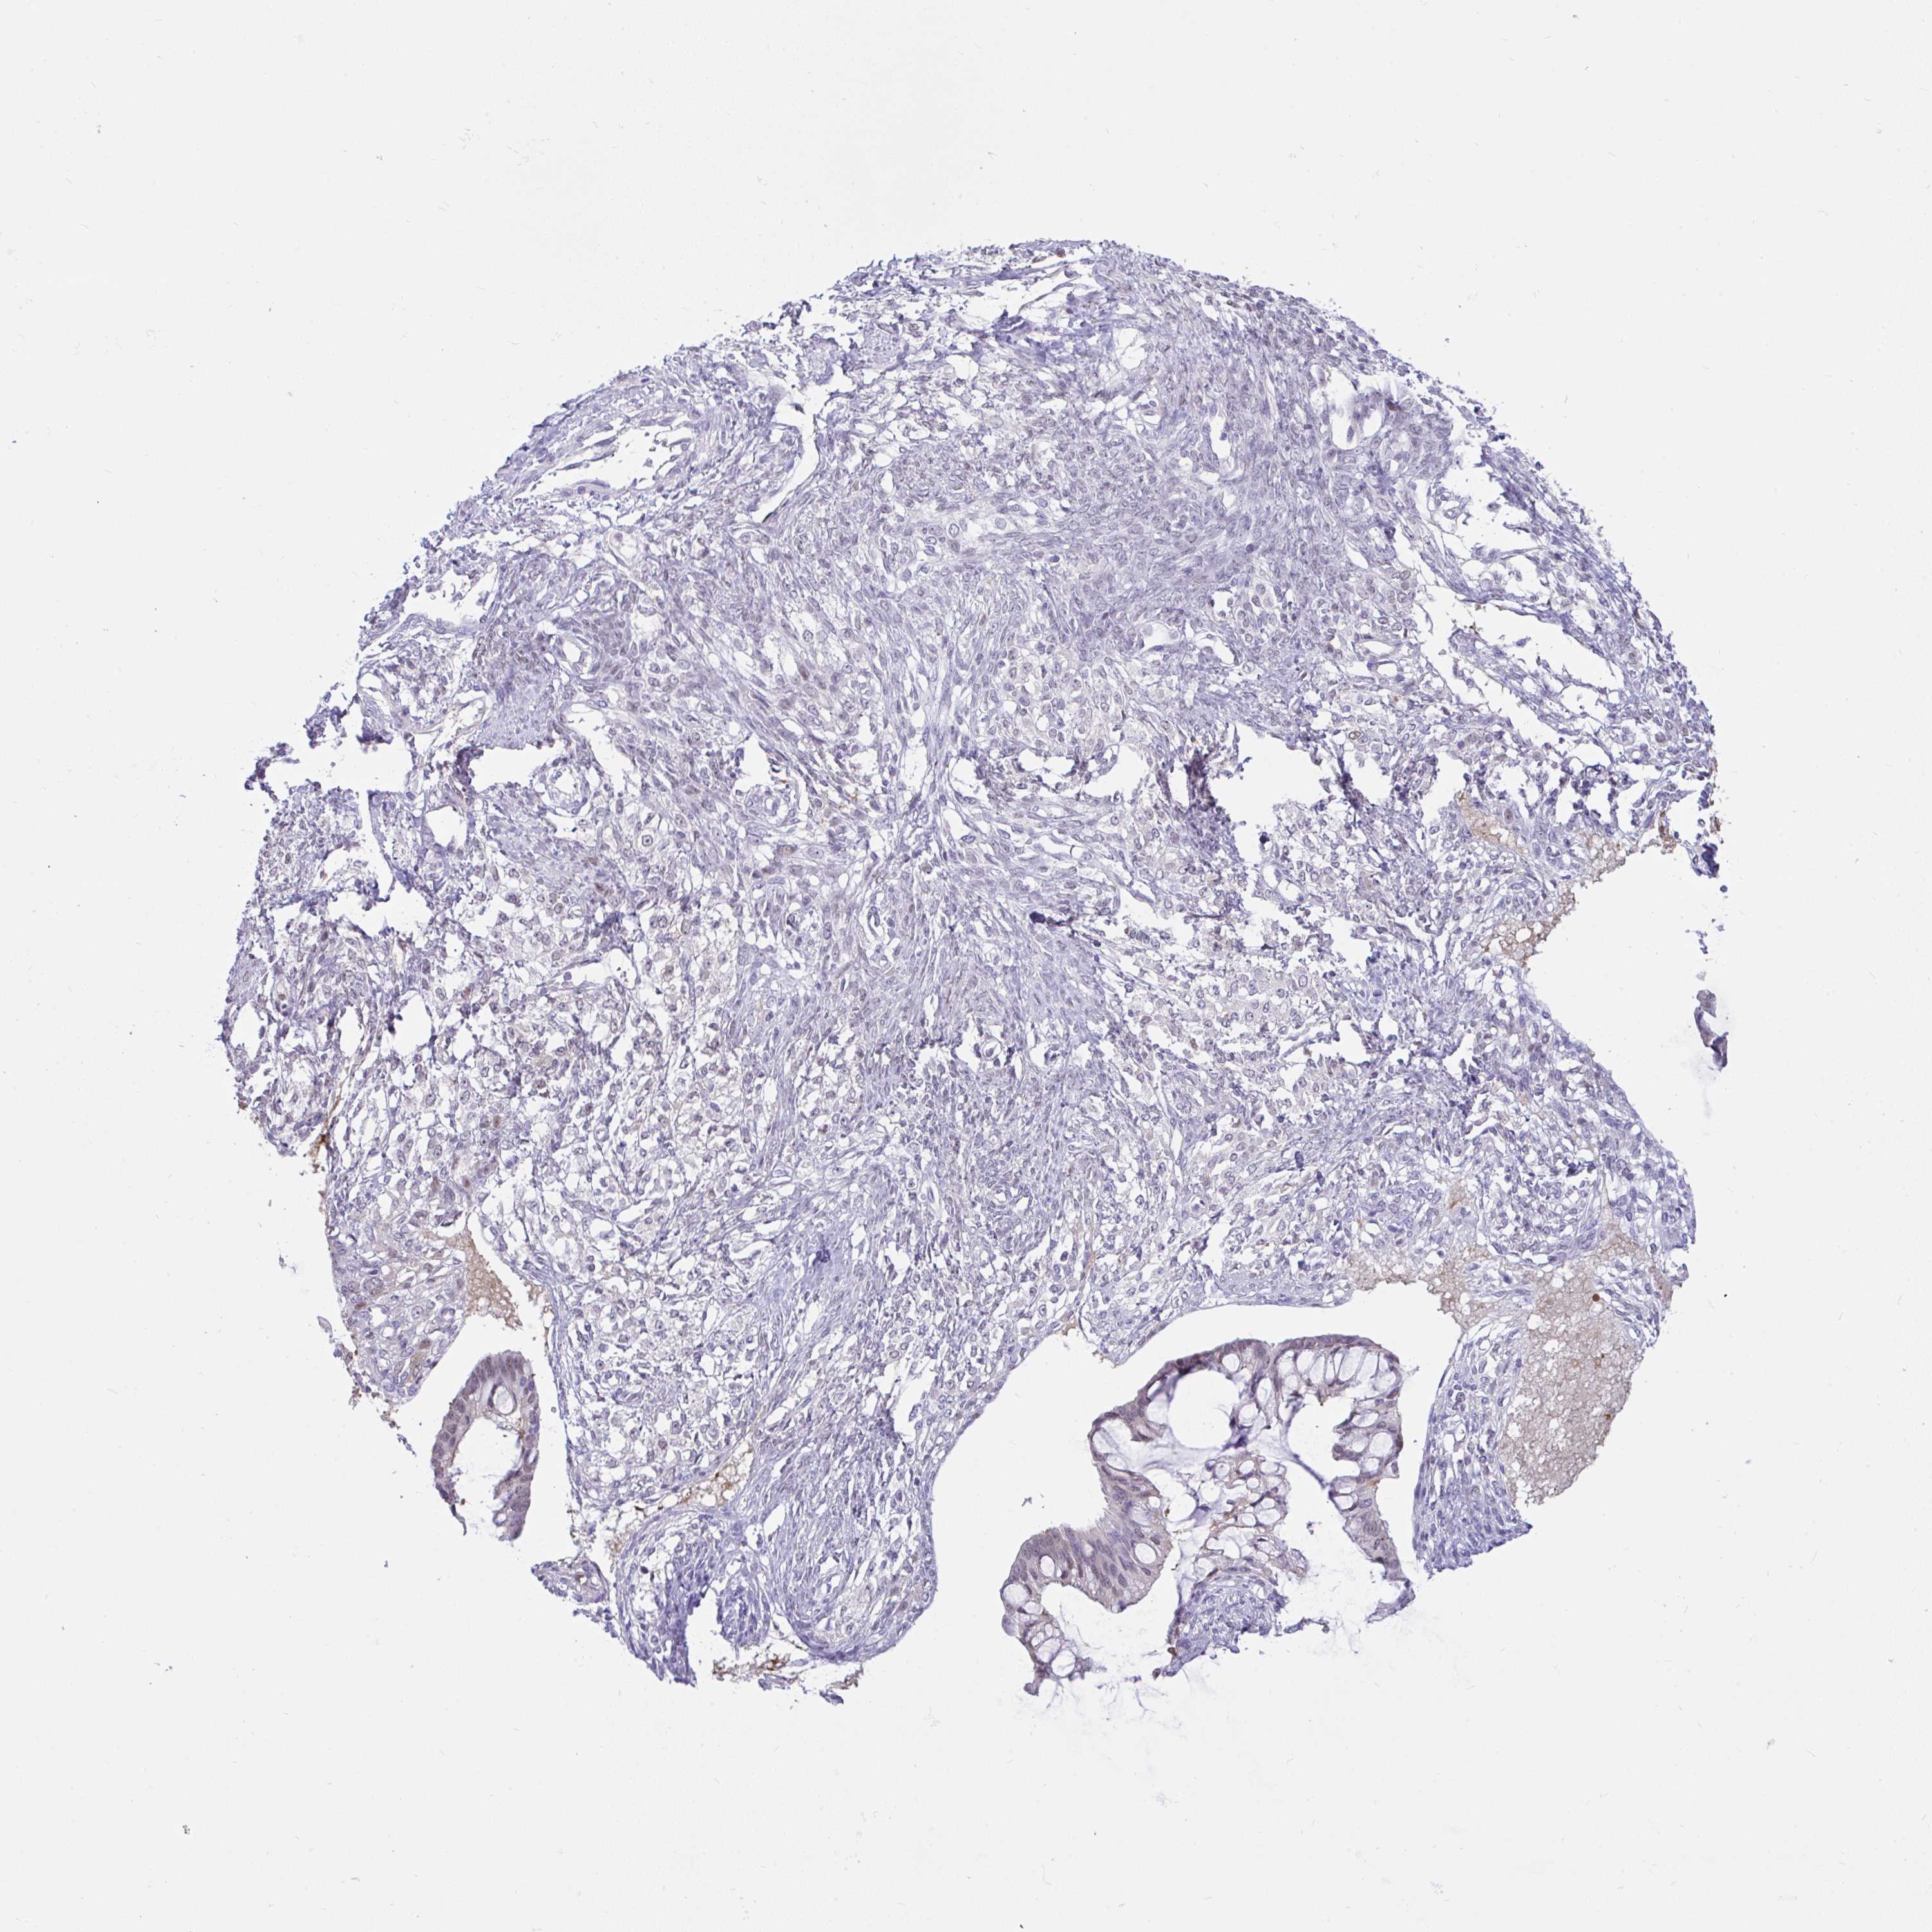

OVARIAN CANCER - Protein expressioni

A mouse-over function shows sample information and annotation data. Click on an image to view it in a full screen mode. Samples can be filtered based on level of antibody staining by selecting one or several of the following categories: high, medium, low and not detected. The assay and annotation is described here.

Note that samples used for immunohistochemistry by the Human Protein Atlas do not correspond to samples in the TCGA dataset.

Antibody stainingi

Antibody staining in the annotated cell types in the current human tissue is reported as not detected, low, medium, or high, based on conventional immunohistochemistry profiling in selected tissues. This score is based on the combination of the staining intensity and fraction of stained cells.

Each image is clickable and will lead to virtual microscopy that enables deeper exploration of all samples and also displays staining intensity scores, fraction scores and subcellular localization as well as patient and tissue information for each sample.

Antibody HPA059356

Staining

High

Medium

Low

Not detected

Intensity

Strong

Moderate

Weak

Negative

Quantity

>75%

75%-25%

<25%

None

Location

Nuclear

Cytoplasmic/membranous

Cytoplasmic/membranous,nuclear

Cystadenocarcinoma, serous, NOS

Carcinoma, endometroid

Cystadenocarcinoma, mucinous, NOS

Carcinoma, NOS